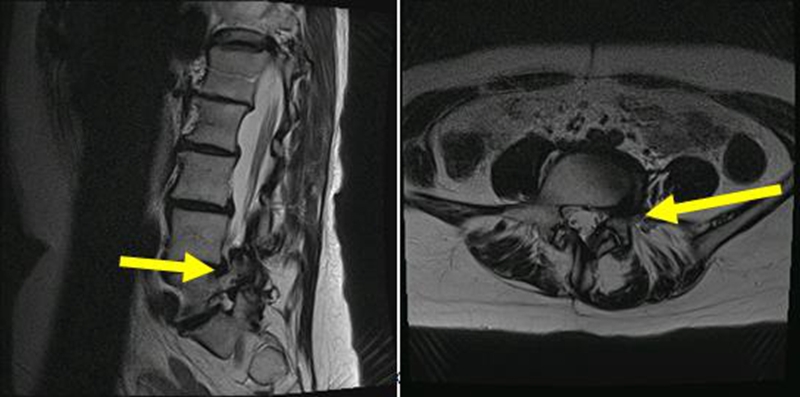

51岁,女性,腰椎术前矢状位明显失平衡,术后多年加重;

期望解决下肢痛及站立问题。

诊断:腰椎局部融合术后,临近节段后凸畸形。

术前X线

予患者行后路PSO截骨,T10-骨盆固定。

术后X线